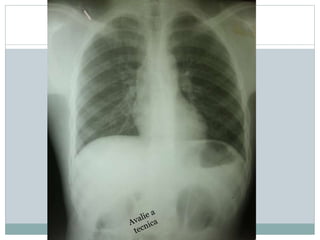

Avalie o raio x , descreve bem a

patologia cardiaca,

Conclusão?

Tecnica:

rotada, pouco penetrado,

revelação boa, tirado deitado e inclinado

Patologia:

• Cardiomegalia grave,

• com atrio esquerdo muito prominente

• Ventriculo esquerdo e atrio direito também

dilatados

• Trama vascular aumentada

Conclusão:

(11 anos, clinicamente IC que agravou ha uma semana)

Raio X tipico de insuficiencia mitral (provavelmente devido FR) com IC

descompensada

• NB como a penetracao é muito diminuida corremos risco de “ ver” lesões

pulmonares amais, neste caso não ha infiltrado pulmonar, apenas congestão

pulmonar!